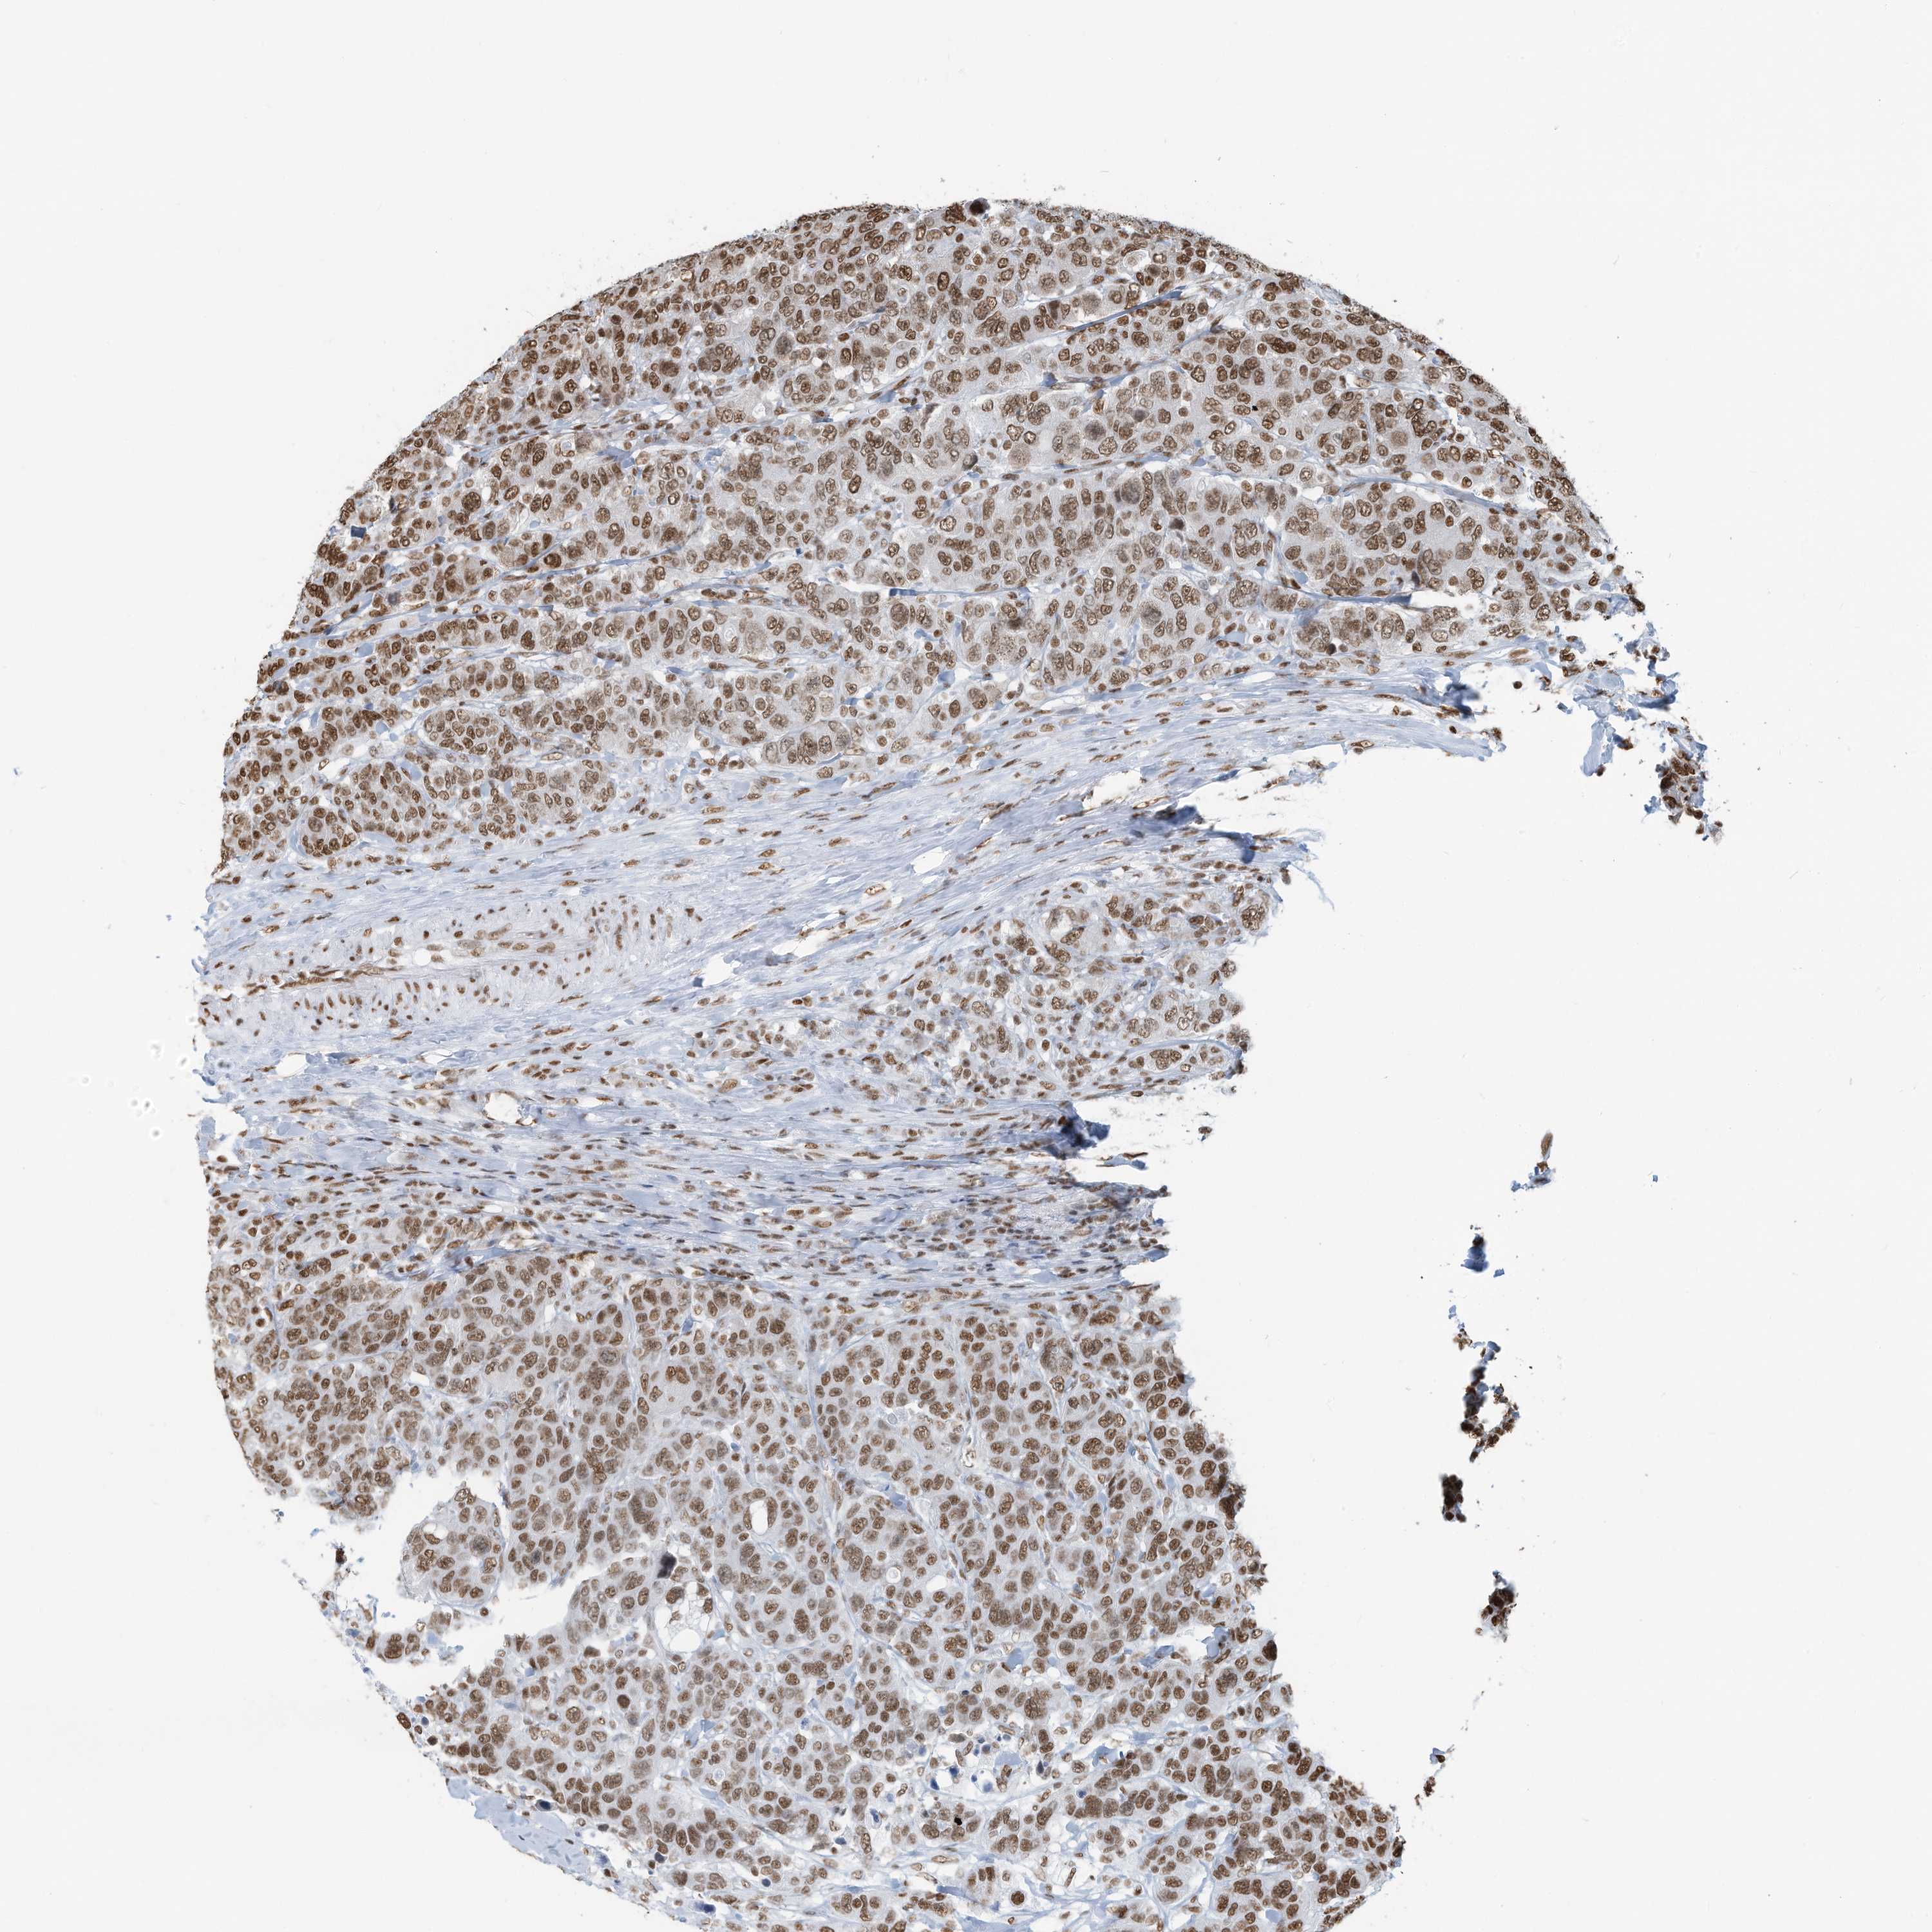

CANCER BREAST CANCER Show tissue menu

BRCA TCGA BRCA VALIDATION PROTEIN EXPRESSION

ANTIBODIES

AND

VALIDATION